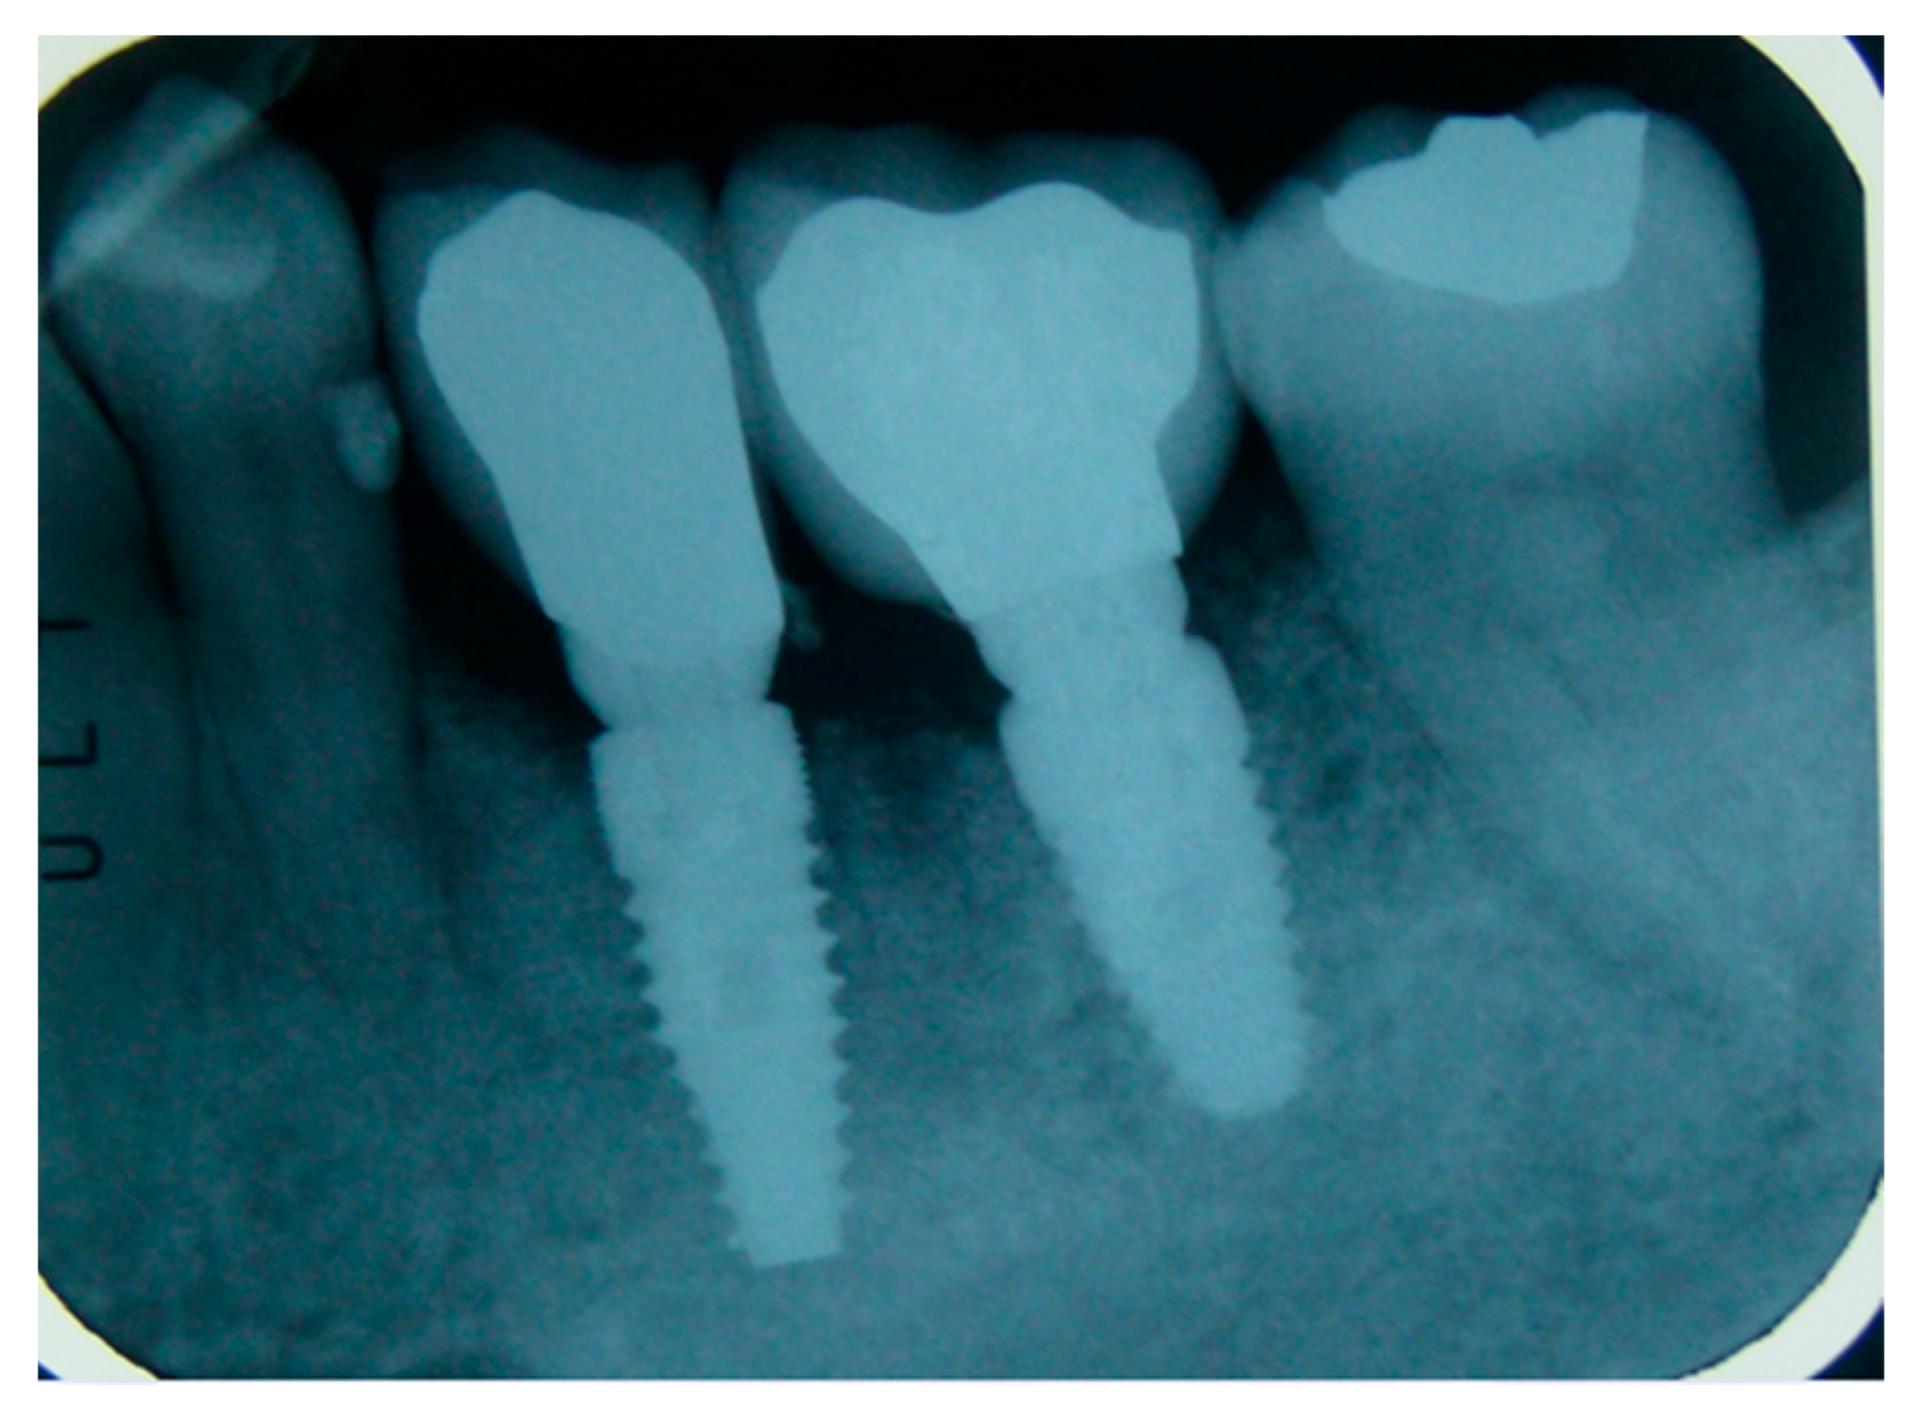

The vertical average defect was 9.16 mm, buccal lateral/palatal 7.0 mm, and mesio-distal 10.3 mm. The measurements were intraoperatively performed with a millimeter periodontal probe. The endodontic material mechanically cleaned before the tooth was placed inside the Tooth Transformer device. The endodontic material was removed using a drill bur with the attention to cut the canal in excess with the aim to remove all the cement. No surgical complications were registered. Pre and post-operative X-rays (section from CBCT) were collected from the same case (Figure 1, Figure 2, Figure 3 and Figure 4). After four months, 13 histological and histomorphometrical evaluations were performed (Figure 5). The Bone Volume/Total Volume average (BV%) was 41.47 (S.D. ± 11.51), the Residual Graft/Total Volume average (Graft%) was 16.60 (S.D. ± 7.09), and the Vital Bone/Total Bone average (VB%) was 21.89 (S.D. ± 9.72). No extraneous material (gutta-percha or cement) was detected in all samples (Table 3).

Figure 1. X-ray, elements 35 and 36 surrounded by a big bone defect.

Figure 2. In the cbct section in zone 36, it is possible to note the bone loss dimension.

Figure 3. The cbct section in zone 36, two months after the Guided Bone Regeneration (GBR). The defect was completely filled using the endodontical treated elements site 3.5 and 3.6 (Italian teeth numeration).

Figure 4. The cbct section in zone 36 after the implants healing, six months after the GBR.

Figure 5. X-ray after 30 months of follow up showing the implant with the prosthesis.